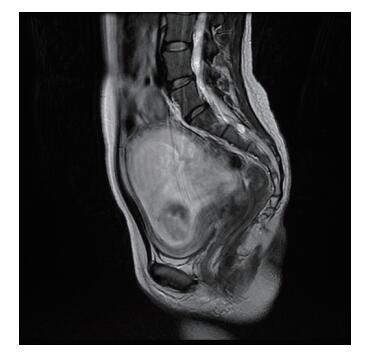

二、实验室及辅助检查血常规:血红蛋白110 g/L,红细胞4.6×1012/L,白细胞18.9×109/L,淋巴细胞2.4×109/L,中性粒细胞16.5×109/L。CRP 60 mg/L,降钙素原0.11 μg/L。产科彩超:宫内妊娠,孕32周,受明显增大的子宫影响,原腹腔肿物不能探及。泌尿系、肝胆胰脾、阑尾超声检查未见异常。盆腹腔MRI提示肠道占位性病变(45 mm×32 mm),见图 1。

图 1 一例妊娠合并回结肠子宫内膜异位症患者的盆腹腔MRI结果 |